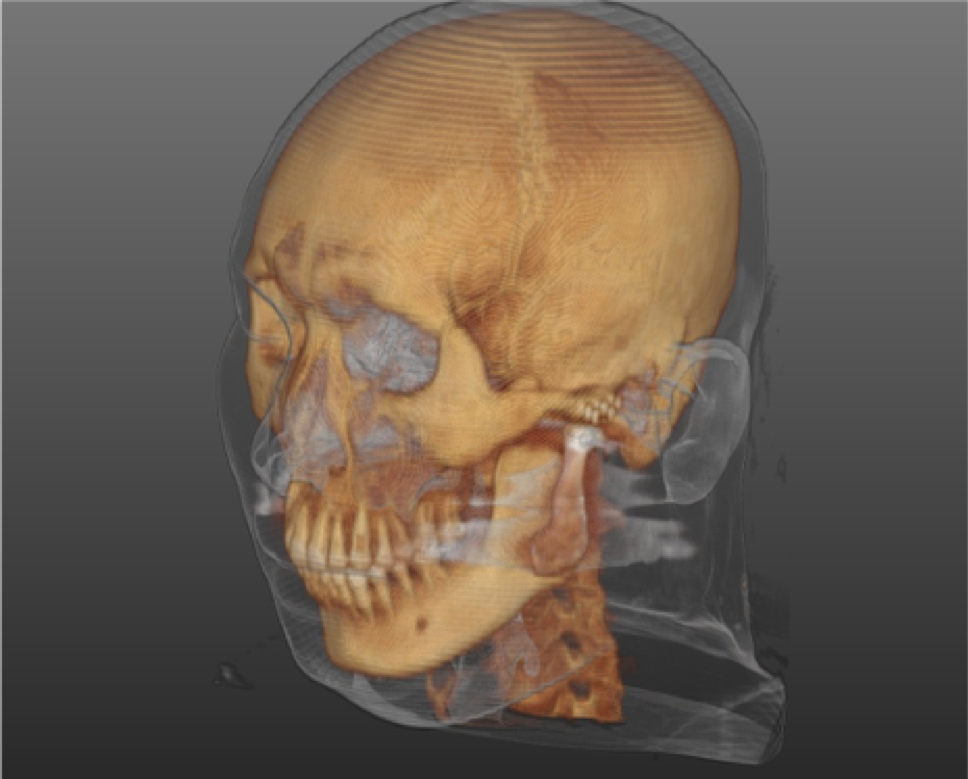

Fig. 2 Postoperative 3D reconstructed CT with TMJ prosthesis, 최대 개구량 30mm